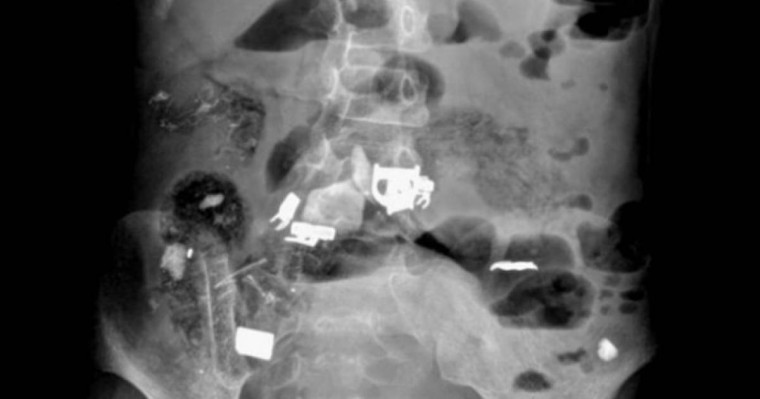

"Ақпан айында облыстық балалар ауруханасында Жаңөзен қаласында тұратын 12 жасар мүгедек балаға шұғыл түрде ота жасалды. Бұл бала (12 жастағы қыз бала) ауруханаға іштің түйіліп ауруы және өте көп мөлшерде құсу шағымымен түсті. Құрсақ қуысы органдарын рентгенге түсіру нәтижесінде, баланың ішінде бөтен заттардың жатқандығы анықталды", - делінген хабарламада.

Дәрігерлердің жедел іс-әрекетінің арқасында, ота барысында қыз баланың ішегінен бөтен заттар (темір, қалам, скотч, шаш) шығарылды.